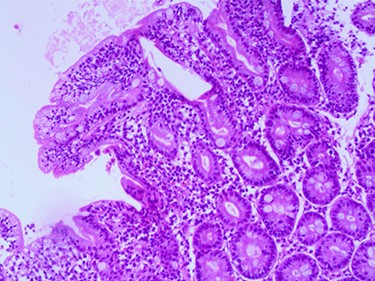

Postoperative ileoileal intussusception after surgical reduction.

A 3.5-year-old Syrian female was admitted to our hospital with complaints of abdominal pain. She had had several episodes of non-bilious, non-bloody vomiting for 36 hours, and her last normal bowel movement was 2 days prior. Although the patient had a history of sickle cell anemia confirmed by electrophoresis from her first year of life, she had not experienced any sickle cell crises and had not needed blood transfusion or hospitalization. She had no history of diarrhea, either. Family history for celiac disease was positive in a second-degree relative. On admission, her vital signs were normal. Blood analysis indicated low hemoglobin (Hgb) concentration of 9.3 g/dl, but other initial laboratory results were normal. Abdominal examination showed tender distended abdomen. Abdominal ultrasonography suggested the presence of intussuscepted bowel in the right iliac fossa with free fluid between the bowels. Hydrostatic reduction (HR) was not successful, so she underwent surgical reduction. Although no lead points were found, there were multiple enlarged mesenteric lymph nodes and edematous ileocecal junction. On the third postoperation day, the patient again developed similar symptoms, and this time ultrasonography revealed IS in the left side of the abdomen. There was no improvement in symptoms for 24 hours, and ultrasonography revealed the same results after an HR attempt. The patient was operated on a second time, and manual ileoileal IS (Fig. 1) reduction and prophylactic appendectomy were performed. The postoperative course was uneventful, and the patient was discharged 3 days later. Three months later, the patient developed abdominal pain, and the diagnosis of IS was confirmed via ultrasonography. This time, IS reduced over 24 hours of observation. As no lead point was found through the later laparotomy, further investigations were conducted. Upper gastrointestinal endoscopy was performed and showed a mosaic pattern of the duodenum mucosa suggestive of CD. On microscopic evaluation, sections reveal advanced atrophy of duodenal villi with occasional intraepithelial lymphocytes (>30/100 IEL). Crypts show moderate hyperplasia; the lamina propria is infiltrated by diffuse mononuclear inflammatory cell infiltrate. Histopathologically, it is compatible with Grade B2 on the new grading system for CD classification (Figs 2–4). The child was then administered with a gluten-free diet. Eight months later, she visited the hospital as outpatient, and examination revealed she was free of any symptoms.